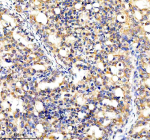

IHC testing of FFPE human brain tissue with CYP7B1 antibody. HIER: steam section in pH6 citrate buffer for 20 min and allow to cool prior to staining.

Immunohistochemistry (FFPE) : 1:50-1:100